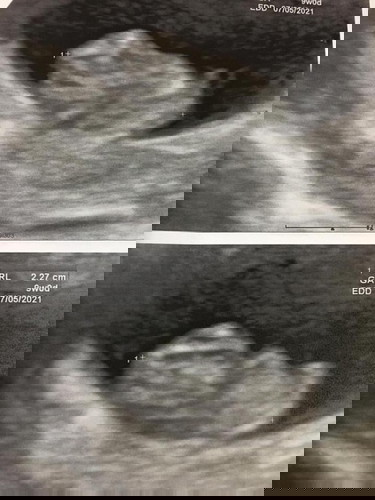

ปรึกษาแม่ๆ ท้อง2 เดือน ผลตรวจเลือดออกมาคือ ผลธาลัสซีเมีย คือเป็นพาหะสาบเบต้าชนิดอี ต้องให้สามีไปตรวจ. อยากทราบว่า เป็นอันตรายต่อลุกไหมคะ. ต้องดูแลตัวเองยังไง. แล้วคลอดลูกมาจะเป็นไหม. ใครมีประสบการแบบนี้บ้าง. กังวลมากคะ